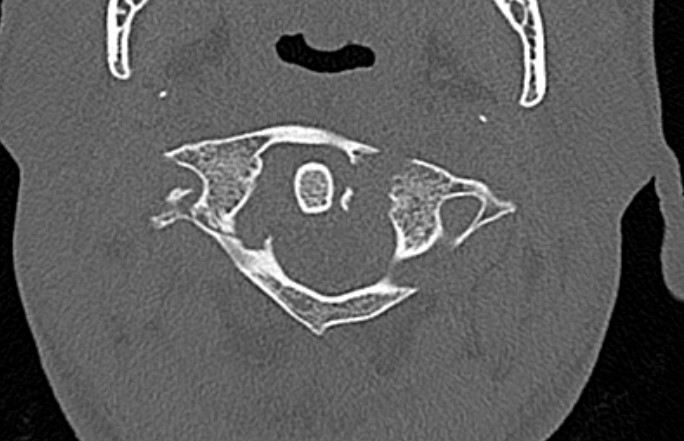

CT

Better defines displacement, ADI, LMD and bony avulsions of the transverse ligament

Avulsionlig avulsion

CT axial slices "Jefferson" (burst) fracture with bony avulsion (blue) of the transverse ligament